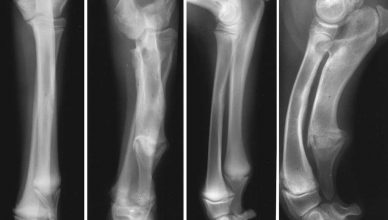

Condrodisplasia en dálmatas, últimos hallazgos

Las displasias esqueléticas abarcan un grupo diverso de trastornos genéticos caracterizados por baja estatura y enanismo. En humanos, se han documentado 771 tipos de displasia esquelética. También se han observado formas similares de estos trastornos en perros.